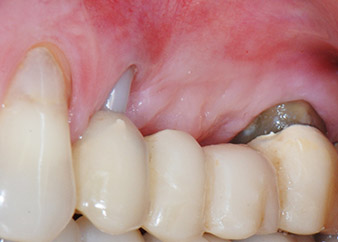

Figures 17 and 18 show the clinical result two months after the surgery. Tooth 24 exhibited reduced mobility of Miller class 1, and the soft tissues were free of inflammation. Probing was avoided at this point of time to prevent reinfection and to avoid violating the epithelial attachment. A control visit was scheduled for reentry and placement of healing abutments, six months after the insertion of the implants.

Two months after the surgery, the patient was pain-free.

At the two-months recall, the mobility of the remaining “dental element” 24 was already reduced from Miller 2 to Miller 1. The soft tissue attachment was on the level of the neighbouring tooth 23. Moreover, there were no endodontic or periodontal symptoms, so its prognosis may have to be readjusted.

However, as most of the buccal and proximal bone is missing and the composite build-up extends to the apical section of the root, a higher reattachment level is not to be expected due to biologic reasons (Sculean et al., 2008).

The sinus floor and GBR procedures will likely result in an alveolar site able to support the implants and a good prognosis (Retzepi and Donus, 2010, Calin et al., 2014). After osseointegration, the implants at positions 25 and 26 will be restored with splinted crowns. If either of the teeth has to be extracted, it will be replaced with an implant-supported single crown.